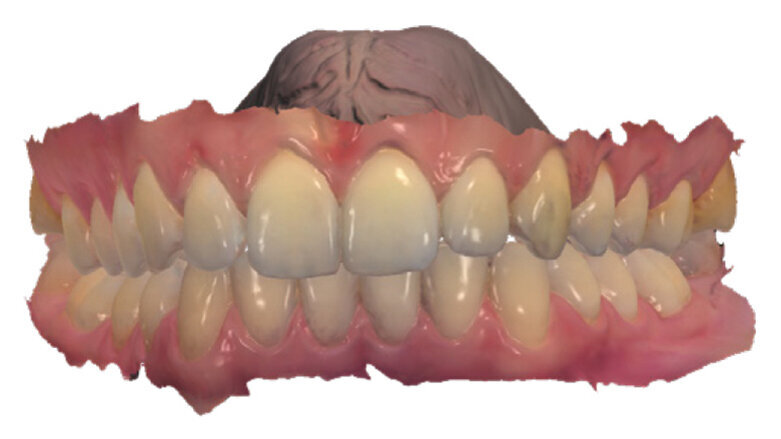

Navzdory mnoha typům dostupných metod ortodontické léčby poskytly průhledné aparáty F22 v tomto případě optimální řešení pro splnění očekávání pacientky (obr. 11–13).

Díky digitálnímu skenování a CAD/CAM plánování poskytuje tento typ léčby velice předvídatelné výsledky. Digitální náhled také umožňuje lékaři případy lépe posoudit a v případě potřeby navrhnout alternativní typ léčby.